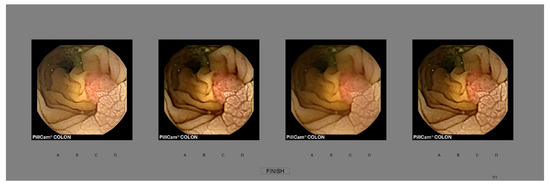

5.2. Dataset

5.3. Subjective Evaluation